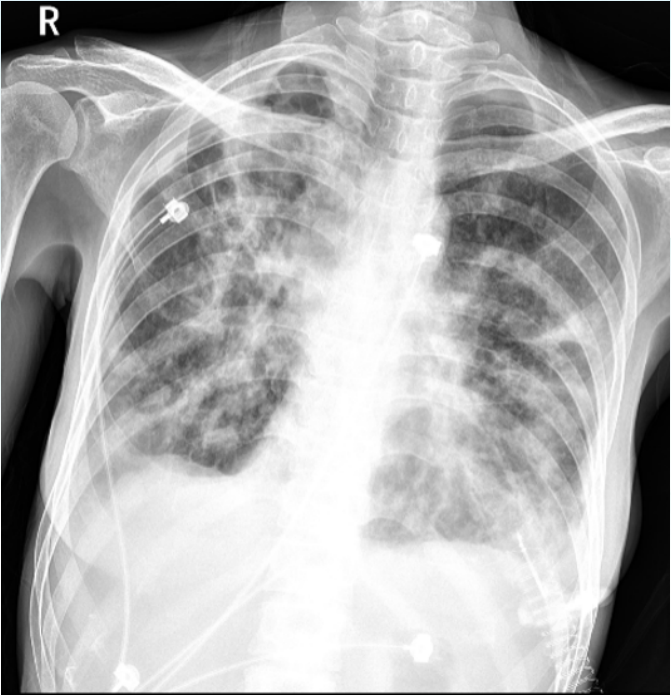

9月26日床旁胸片提示:左上肺实变较前吸收(图4)

图片

4  患者床旁胸片(2024-09-26)

2024年10月10日普通病房床旁胸片示:双肺透光度不均匀,双肺纹理增多、紊乱,双肺见散在斑片影及絮状影,双肺门影显示不清;膈面显示欠清,双侧肋膈角变钝。病灶较前(2024-09-26)增多;双侧胸腔少-中量积液可能,较前增多(图7)

7  床旁胸片(2024-10-10)

10月28日脱机拔管, 复查胸片: 双肺渗出和实变影、双侧胸腔积液较前明显吸收(图10)

10  复查床旁胸片(2024-10-28)